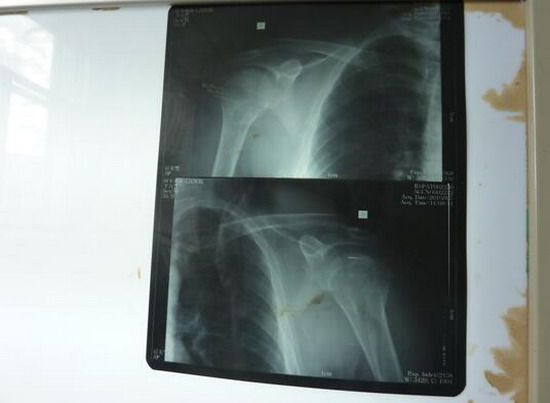

众所周知,骨科医生手术离不开器械和设备,在这里,每台骨科手术都需要他亲自找钢板、螺钉和克氏针等材料。材料不合适,他亲自修整;没有C臂,手术完全靠经验。有时实在想打退堂鼓,但是每每看到患者期盼的眼神和淳朴的话语,他是真心无法拒绝。两月来,他听到患者最多的一句话就是:胡主任,您就放心大胆去做,做好了,我们感谢您,做不好,这是神的旨意,我们不怪您。听到这样的话,谁会忍心拒绝,谁不尽心尽力。每次手术,他都尽量带着科室的医生去做,至今,已参加带教手术20余例,其中新技术新项目6例,分别是:三踝骨折并胫骨下端骨骺分离切开复位内固定术;胫骨开放性粉碎性骨折清创复位外固定架固定术;取骨术与植骨术;肱骨外科颈骨折切开复位内固定术;骨盆骨折切开复位内固定术;巴通骨折切开复位内固定术。股骨颈骨折人工股骨头置换术是阿里地区第二例手术,在当地也产生了很大的社会影响。他参加带教的常规手术有:锁骨骨折切开复位内固定术;肱骨髁上骨折切开复位内固定术;股骨干骨折切开复位内固定术;胫骨干骨折切开复位内固定术;内踝骨折切开复位内固定术;内、外踝骨折切开复位内固定术;多指畸形矫形术;清创缝合术;断指残端修整术;腱鞘囊肿切除术等。指导或参与手法复位石膏固定10余人次。通过带教,规范了骨科手术的操作技术,提高了手术操作水平和技巧。时至今日,没有一例因为技术原因而转走的骨科病人,基本做到中组部提出的中病不出地区的援藏目标。

肱骨外科颈及肱骨头骨折切复内固定

股骨颈骨折股骨头置换